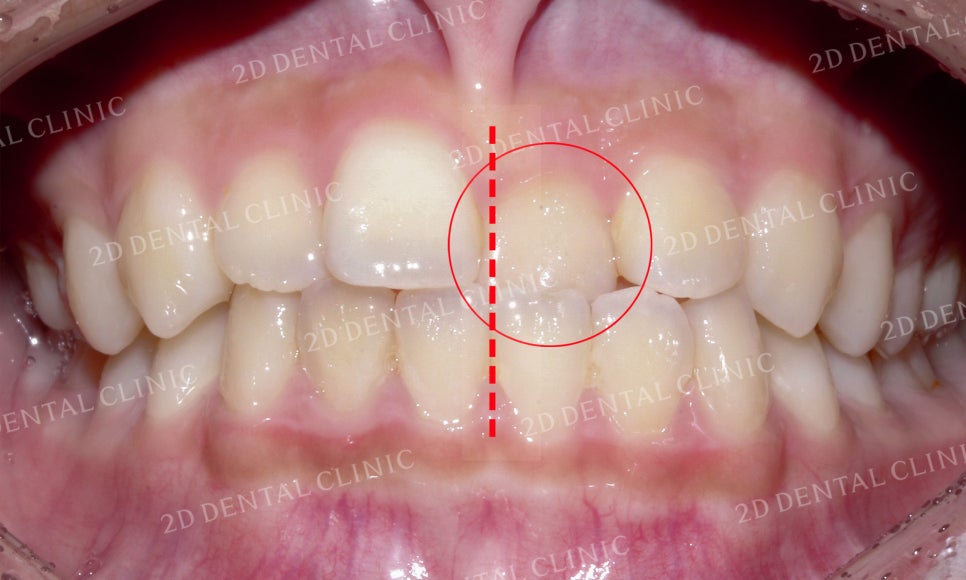

전치부의 치아들을 자세히 살펴보면

상악 좌측 중절치의 반대교합 영향으로

상하악의 정중선도 틀어진 모습인데요,

이러한 문제들로 상악의 절단연 또한

삐뚤삐뚤한 모습입니다.